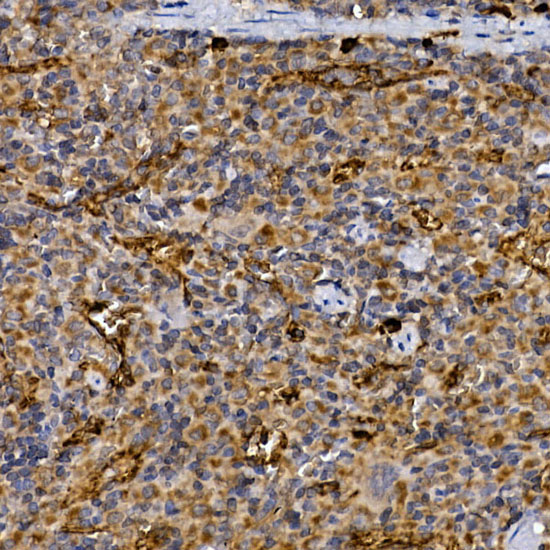

Facts about Dipeptidyl peptidase 4.

| Gene Name: | DPP4 |